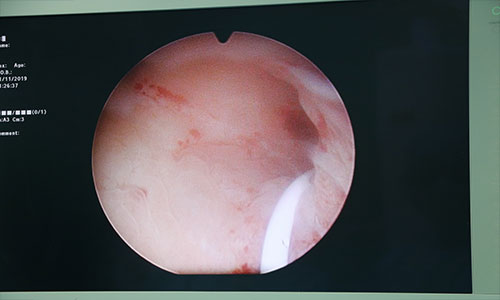

انجام جراحی پیشرفته سنگ کلیه به روش بسته (PCNL) توسط دکتر امیر عباس شه دوست فوق تخصص اندوارولوژی در بیمارستان فوق تخصصی سینا اراک در تاریخ 20 آبان ماه 1398 # این عمل توسط گروه ارولوژی بیمارستان سینا از 2 سال پیش راه اندازی گردیده است . از مزایای این روش ، خروج سنگهای کلیه در یک جلسه و با کمترین برش جراحی و حداقل زمان بستری می باشد .